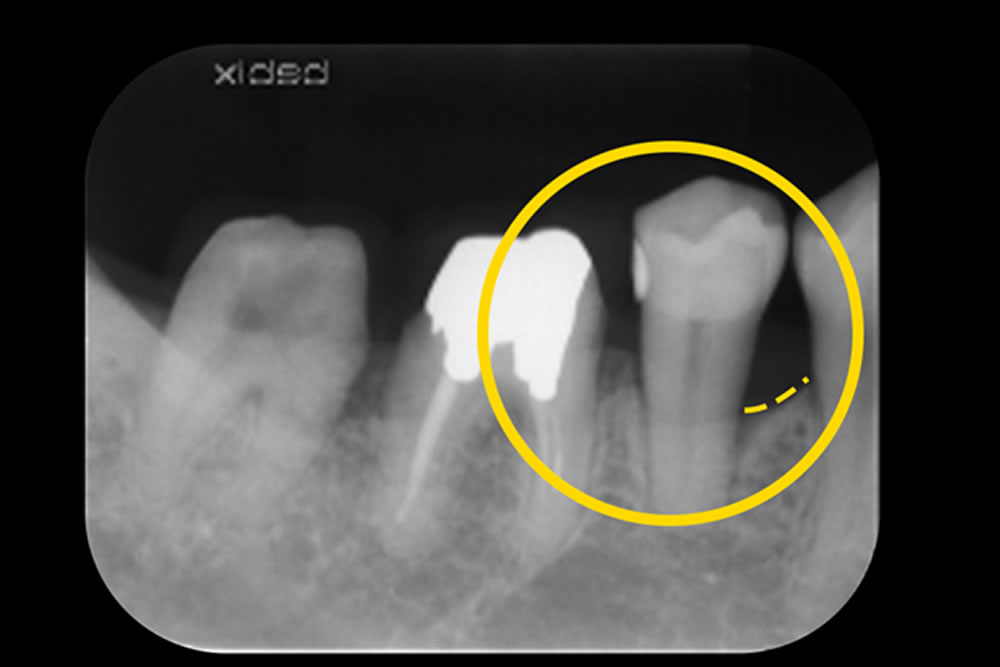

MINSTによる低侵襲な重度歯周病治療症例

| 主訴 | 歯がグラグラする |

| 治療内容 | ・低侵襲非外科治療(MINST)「歯茎を切らない歯周病治療」 ・レーザーペリオ治療 |